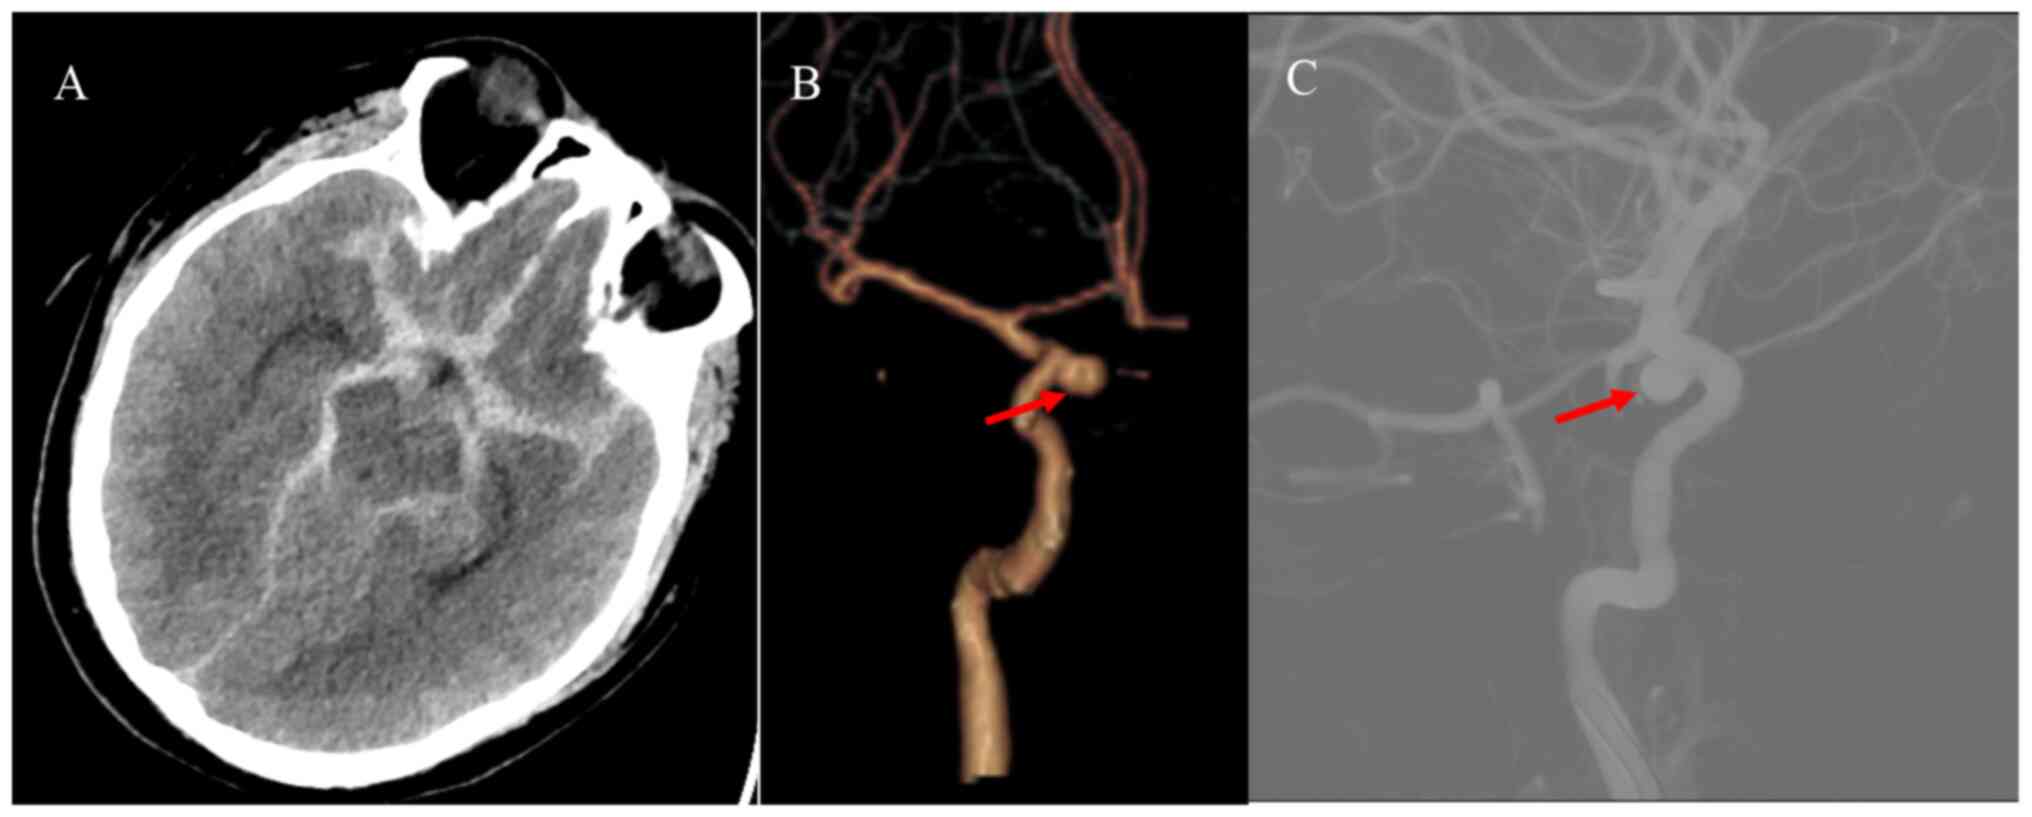

A 40-year-old male patient with a history of hypertension presented to the emergency department of Peking University People's Hospital (Beijing, China) in December 2019 with the complaint of headache for one day, sudden onset of nausea, vomiting and loss of consciousness for 4 h. Neurological examination revealed a Glasgow Coma Scale (GCS) score of 14 (E3V6M5). The patient was a habitual drinker and reported that no immediate family members had experienced any similar cerebrovascular events. The patient had no history of trauma, lumbar puncture or bleeding disorders. The patient was admitted to the emergency department of Peking University People's Hospital (Beijing, China). His blood pressure was controlled through the infusion of urapidil hydrochloride (2-4 ml/h) and his vital signs were stabilized using monitoring equipment and nimodipine administration (2-4 ml/h, 14 days), as described previously (6,7). Cranial computed tomography (CT) and CT angiography (CTA) were performed at the earliest. Brain CT and CTA (Fig. 1A and B) indicated diffuse SAH and an aneurysm in the right internal carotid artery. Thus, a digital subtraction angiography (DSA) examination was scheduled immediately. DSA revealed that the aneurysm was located in the inferior wall of the C5 segment of the right internal carotid artery, with the following characteristics: Aneurysm neck 3 mm and diameter 4x6 mm (Fig. 1C). The patient was placed under general anesthesia 9 h after the bleeding occurred and the intracranial aneurysm was embolized using a coil interventional embolization technique. DSA indicated that the patient's aneurysm was densely packed without contrast retention (Fig. 2A and B). The patient was diagnosed with a right internal carotid artery aneurysm and hypertension.

Figure 1

Preoperative imaging examination of the patient. (A) Initial brain CT showing diffuse subarachnoid hemorrhage. (B) Reconstructive CT angiogram and (C) digital subtraction angiography displaying the C5 segment of the right internal carotid artery aneurysm (red arrows). CT, computed tomography.